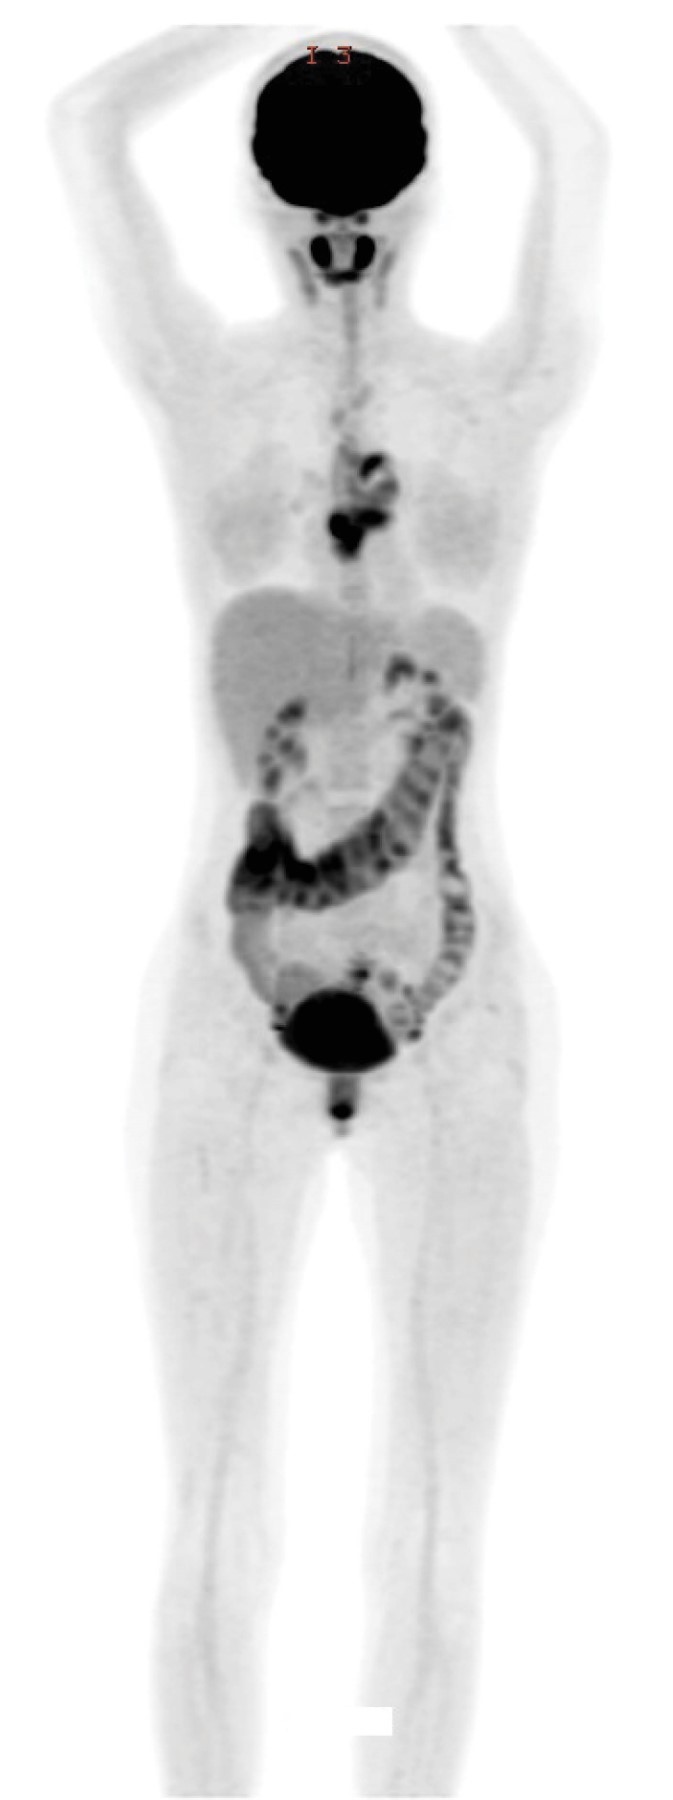

Introducción: el sarcoma mieloide, también conocido como sarcoma granulocítico o cloroma, es una neoplasia maligna resultante de la infiltración de células mieloides inmaduras en tejidos extramedulares, con una incidencia estimada de 2.5-9.1% en pacientes con leucemia mieloide aguda (LMA). El corazón es un sitio poco común de aparición (< 1%). Actualmente, no existen pautas diagnósticas ni de tratamiento firmemente establecidas para esta condición. Caso clínico: paciente femenino de 21 años con antecedente de leucemia mieloide aguda (translocación 9:11), diagnosticada a los 16 años. Tras recibir quimioterapia logró la remisión en octubre de 2019. Fue referida para seguimiento en diciembre de 2021, presentando síndrome consuntivo, palpitaciones y disnea (NYHA II). Conclusiones: este caso resalta la rareza del sarcoma mieloide cardiaco y subraya la necesidad de utilizar imagenología multimodal en el diagnóstico y seguimiento. Además, destaca la relevancia de establecer rutas asistenciales especializadas con una perspectiva cardio-onco-hematológica en México.

Figura 3